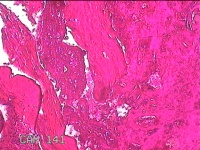

宫腔内容物

性别

女

年龄

28岁

临床诊断

不全流产?

一般病史

人流术后1月余,发现宫腔异常回声4天。

标本名称

大体所见

灰白暗红色不规则碎组织3x2.8x0.8cm一堆。

见胎盘绒毛。